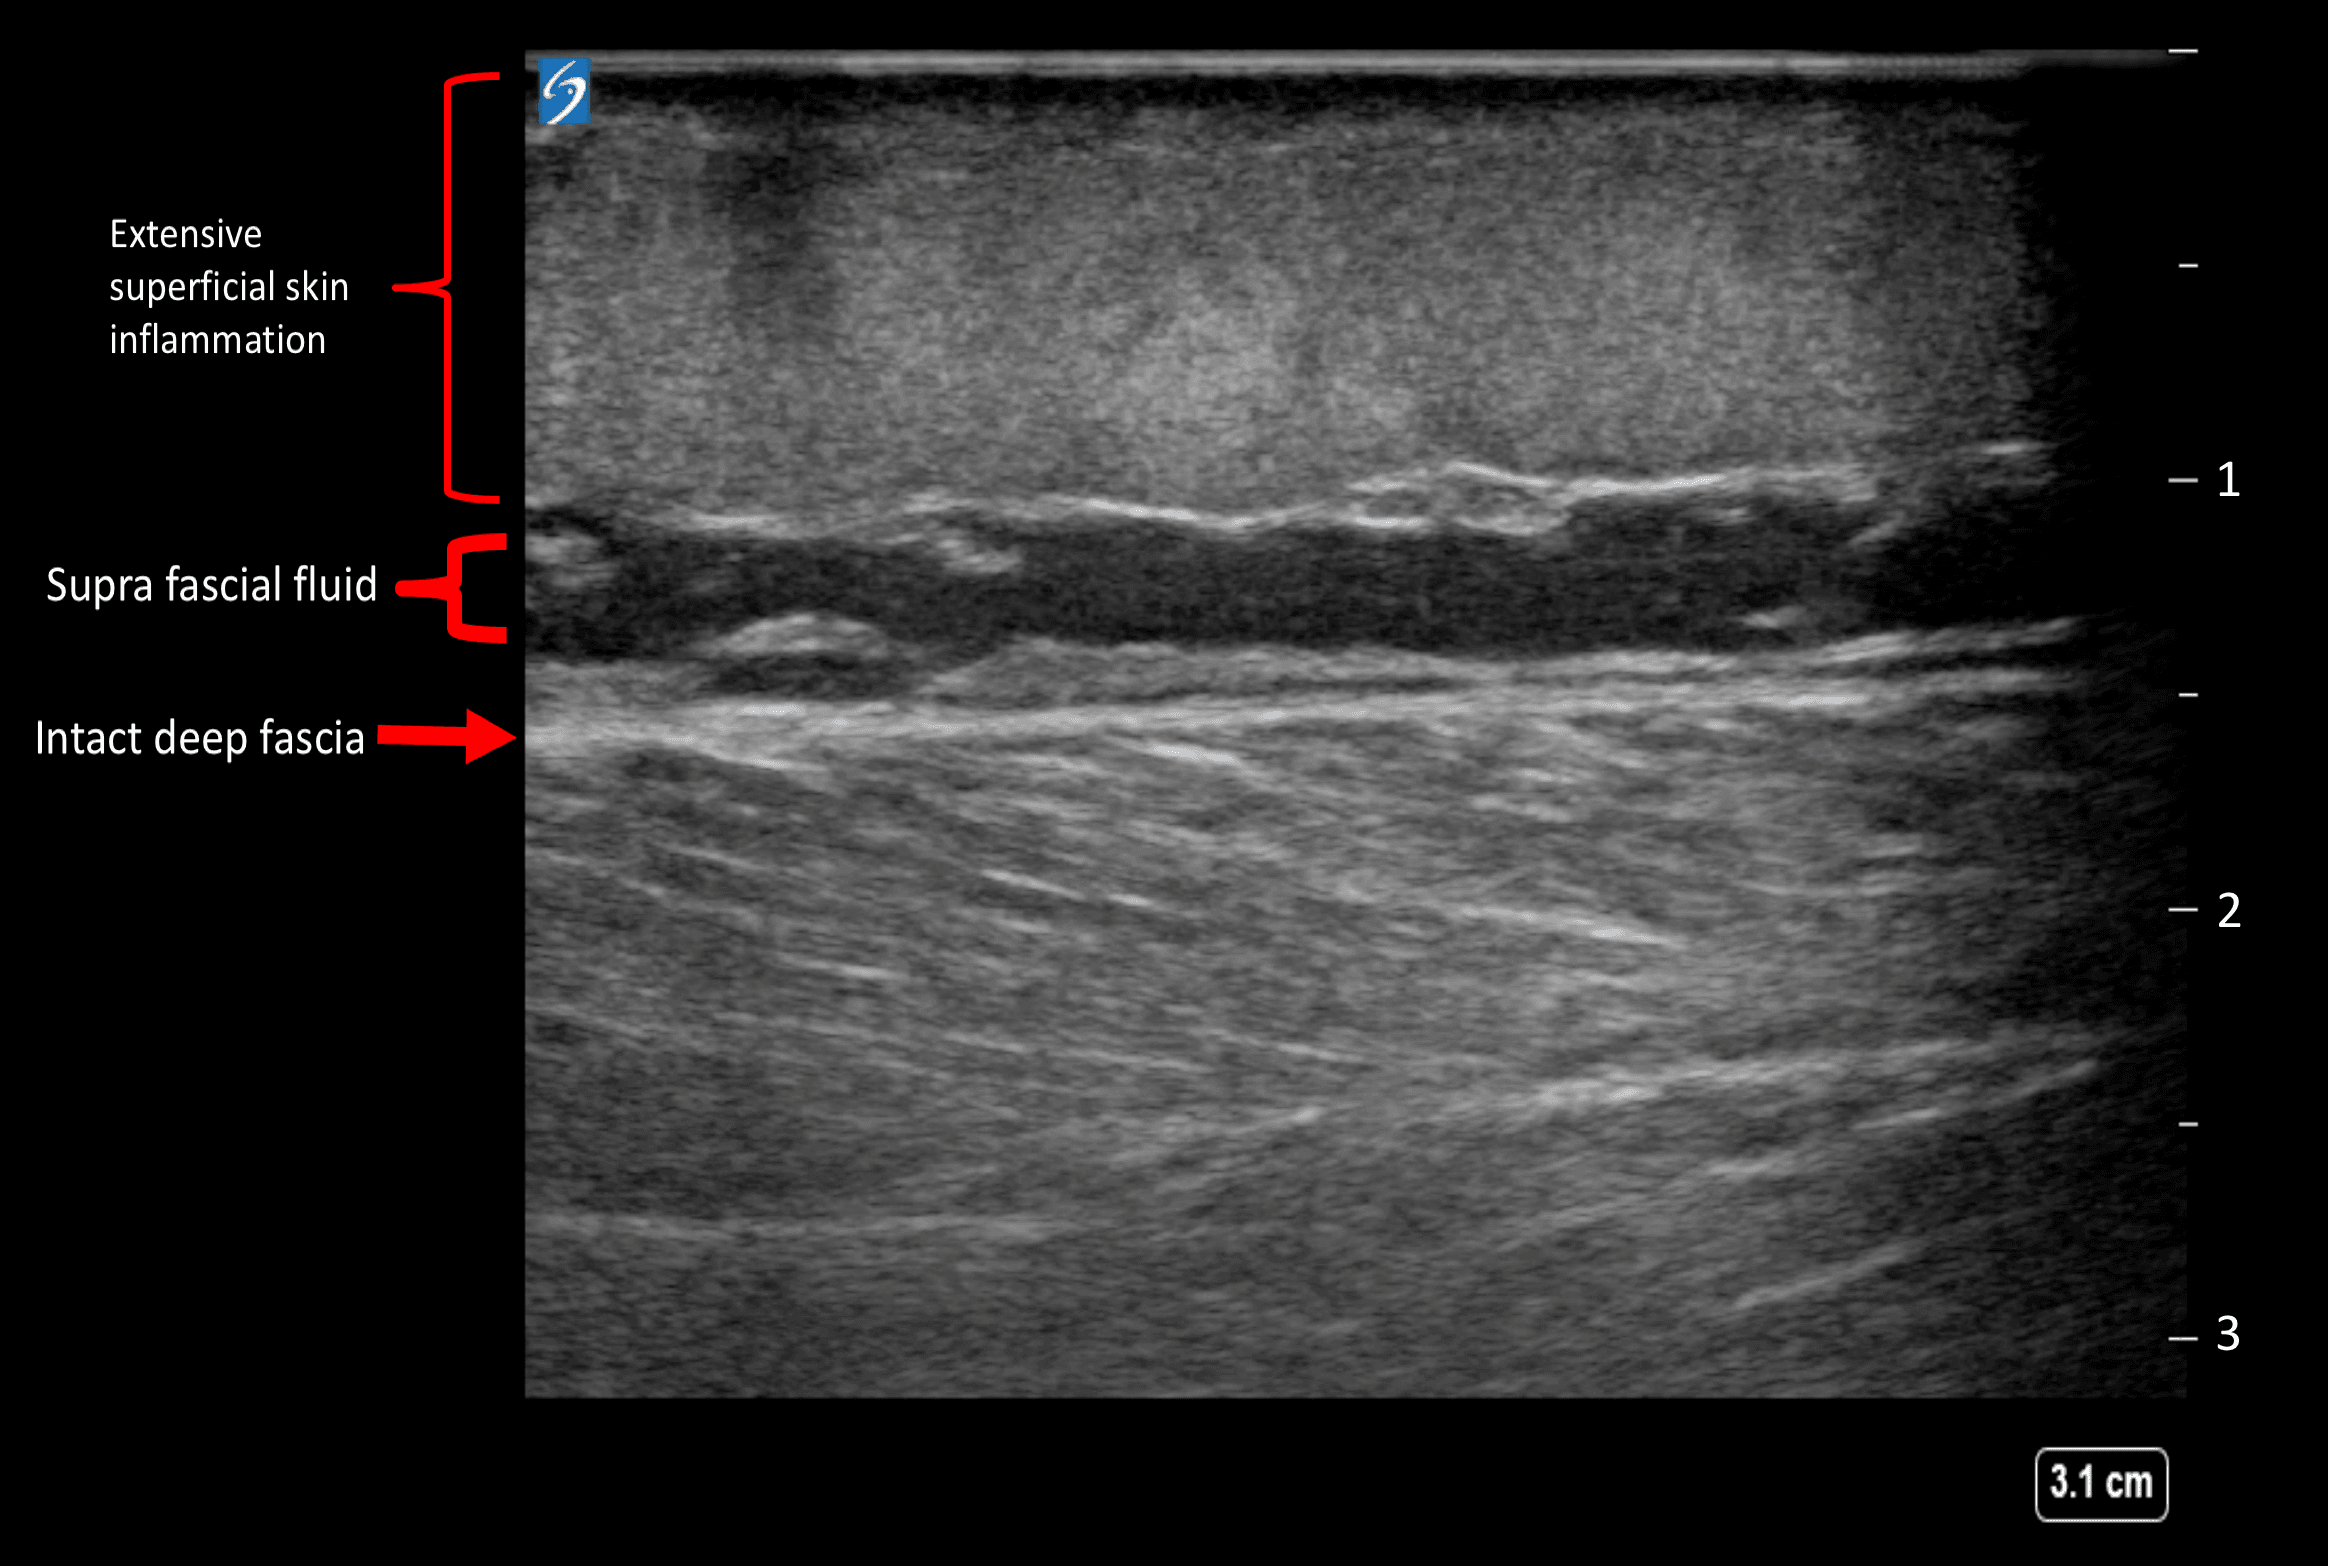

A 24-year-old female of African descent, presented to Rashid hospital trauma center with complaint of painful right leg swelling of one week duration. The patient was sick looking & drowsy. Vitally she was febrile with 38.2o C, and tachycardia of 110 bpm. Local examination of the leg showed cellulitis changes with multiple blisters and necrotic patches (Figure 1). Laboratory tests showed leukocytosis of 14.4 10^3/μL (3.6-11 10^3/μL), Hb 14.1 g/dL (11-15 g/dL), hyponatremia of 125 mmol/L (136-145 mmol/L), CRP 560.9 mg/L (0.3-5 mg/L) and procalcitonin 50.6 ng/mL (more than 10 ng/mL high likelihood of sever sepsis), and LRINEC score 6.

Figure 1. Cellulitis changes with multiple blisters & necrotic patches.

Urgent surgical consultation was obtained and broad-spectrum antibiotics were initiated. Soft tissue ultrasound was performed by linear probe and showed superficial cellulitis with no fascia thickening or sub-fascial fluids seen (clean fascia sign) as per Figure 2. Due to the high clinical suspicion, the patient was posted for urgent surgical debridement for possible necrotizing fasciitis. Intraoperative findings were only positive for superficial inflammatory process; the fascia was found healthy and intact. The patient was labelled as a case of complicated erysipelas and managed with daily dressing and antibiotics. The patient improved over a period of 2 weeks and was discharged home successfully.